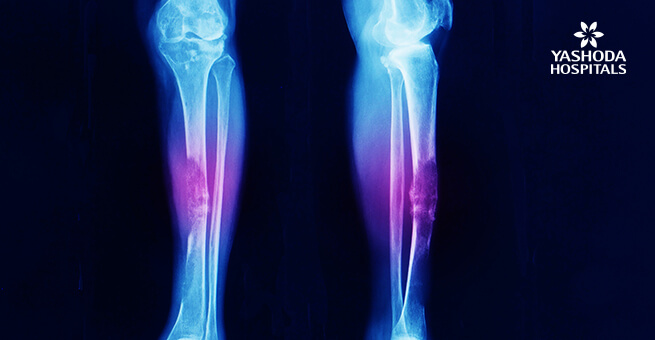

- Bone pain- Minor injury or no injury at all leading to a broken bone/ fracture.

- The doctor advises imaging tests depending on the situation. Tests that are advised are X Rays which are done to diagnose problems in the bone, MRI is done to diagnose connective tissue problems and other tests like CT scan, bone scans and PET (positron emission tomography) can be advised further.

- Sarcomas formed in bones called as Osteosarcoma